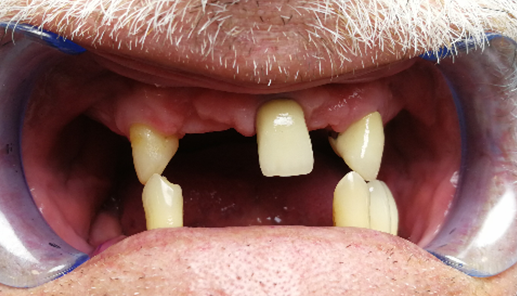

Мы сталкиваемся со случаями как на фото несколько раз в месяц.

Наши врачи никогда не попрекнут пациента, наоборот изучат ситуацию и помогут решить проблему быстро и безболезненно.

Цель врача и пациента – прийти к такому результату.